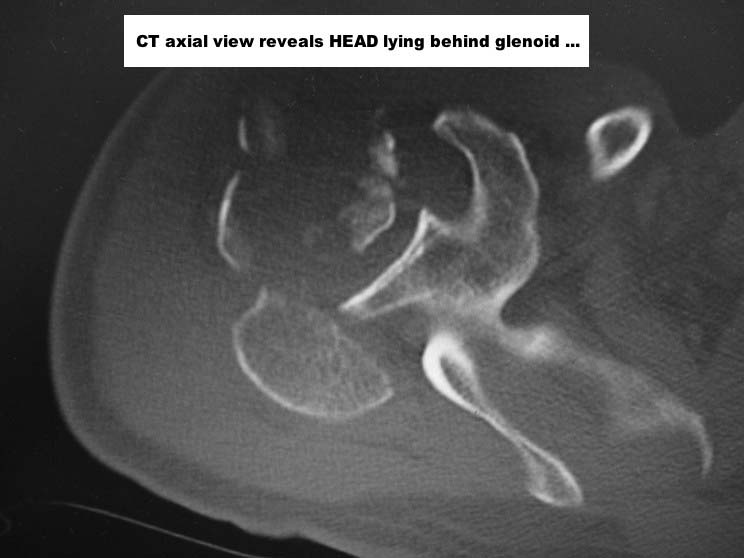

Here are some photos, of chronic, locked, 4 part posterior dislocation, 2 months old, that I did September/2011. Patient is 67, very, very active - had a really reasonable, honest clinical result ...

Photos attached ...